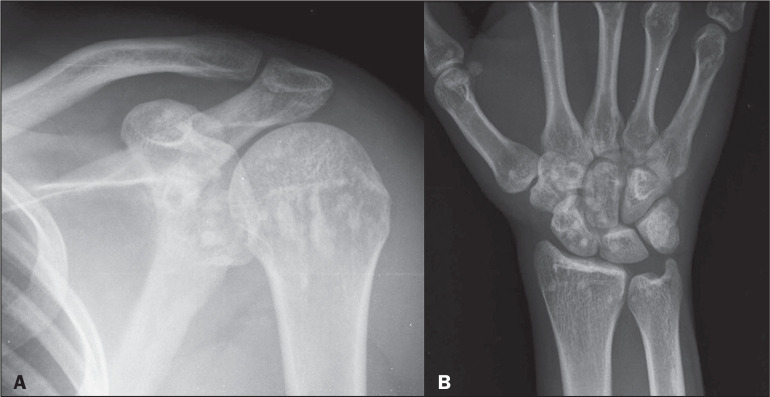

硬化性骨发育不良包括骨密度异常,分为遗传性和非遗传性形式。主要通过x线摄影诊断,通常是偶然发现的。在遗传形式中,以下是最突出的:骨质疏松症、骨质疏松症、多发性骨干硬化(肋病)、纹状骨病和Camurati-Engelmann病。在非遗传性形式中,髓内骨硬化和骨质疏松症具有特定的影像学特征。主要的鉴别诊断包括成骨细胞转移、结节性硬化症和肾性骨营养不良,由于它们的相似性,需要仔细鉴别。

Sclerosing bone dysplasias encompass abnormalities in bone density, divided into hereditary and nonhereditary forms. Primarily diagnosed through radiography, they are often incidental findings. Among the hereditary forms, the following stand out: osteopetrosis, osteopoikilosis, multiple diaphyseal sclerosis (ribbing disease), osteopathia striata, and Camurati-Engelmann disease. Among the nonhereditary forms, intramedullary osteosclerosis and melorheostosis present specific radiographic characteristics. The main differential diagnoses include osteoblastic metastases, tuberous sclerosis, and renal osteodystrophy, requiring careful differentiation because of their similarities.